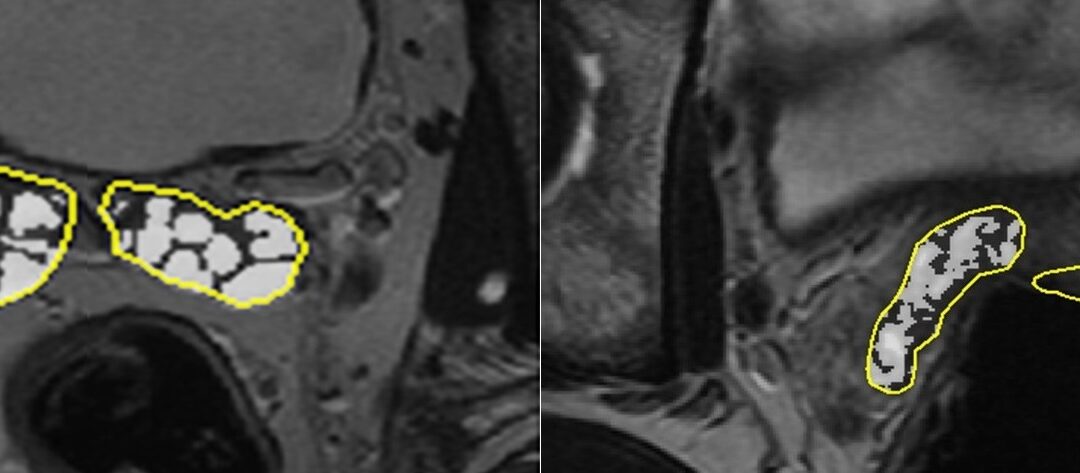

This articles focuses on the volume reduction of fluid within the seminal vesicles after ejaculation, as shown in MRI.

• Seminal vesicle volume significantly reduced 24 h post-ejaculation remaining reduced at day

• Seminal vesicle fluid volume significantly increased from day 1 to day 3 post-ejaculation

• 3-day abstinence from ejaculation is required to ensure maximal seminal vesicle distension